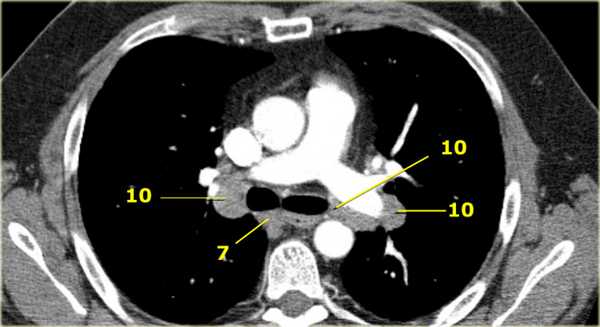

7. Подкаринальные лимфатические узлы

Эти лимфатические узлы расположены ниже уровня бифуркации трахеи (карины), но не относятся к нижнедолевым бронху и артерии. Справа они располагаются каудальнее нижней стенки промежуточного бронха. Слева они располагаются каудальнее верхней стенки нижнедолевого бронха. Слева лимфатический узел 7 группы справа от пищевода.